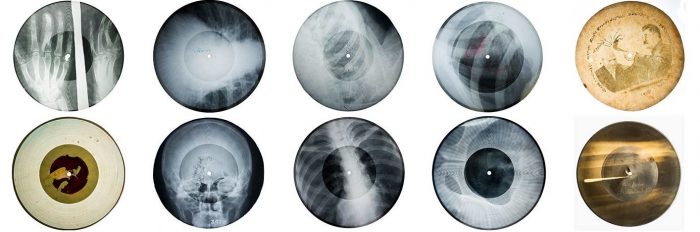

Рентгеновская плёнка оказалась идеальным материалом — она хорошо резалась, и звук на ней фиксировался вполне сносно . Диски вырезали размером примерно 18 см, а центральное отверстие прожигали сигаретой . Запись велась на скорости 78 оборотов в минуту .

Качество, разумеется, было ужасным. Шипение и треск заглушали музыку, а срок службы таких пластинок составлял всего 5–10 проигрываний . Но покупателей это не останавливало. Цена одной «кости» составляла от 1 до 1,5 рублей . Для студентов, которые были основной аудиторией, это были ощутимые деньги, но возможность прикоснуться к запретному перевешивала.